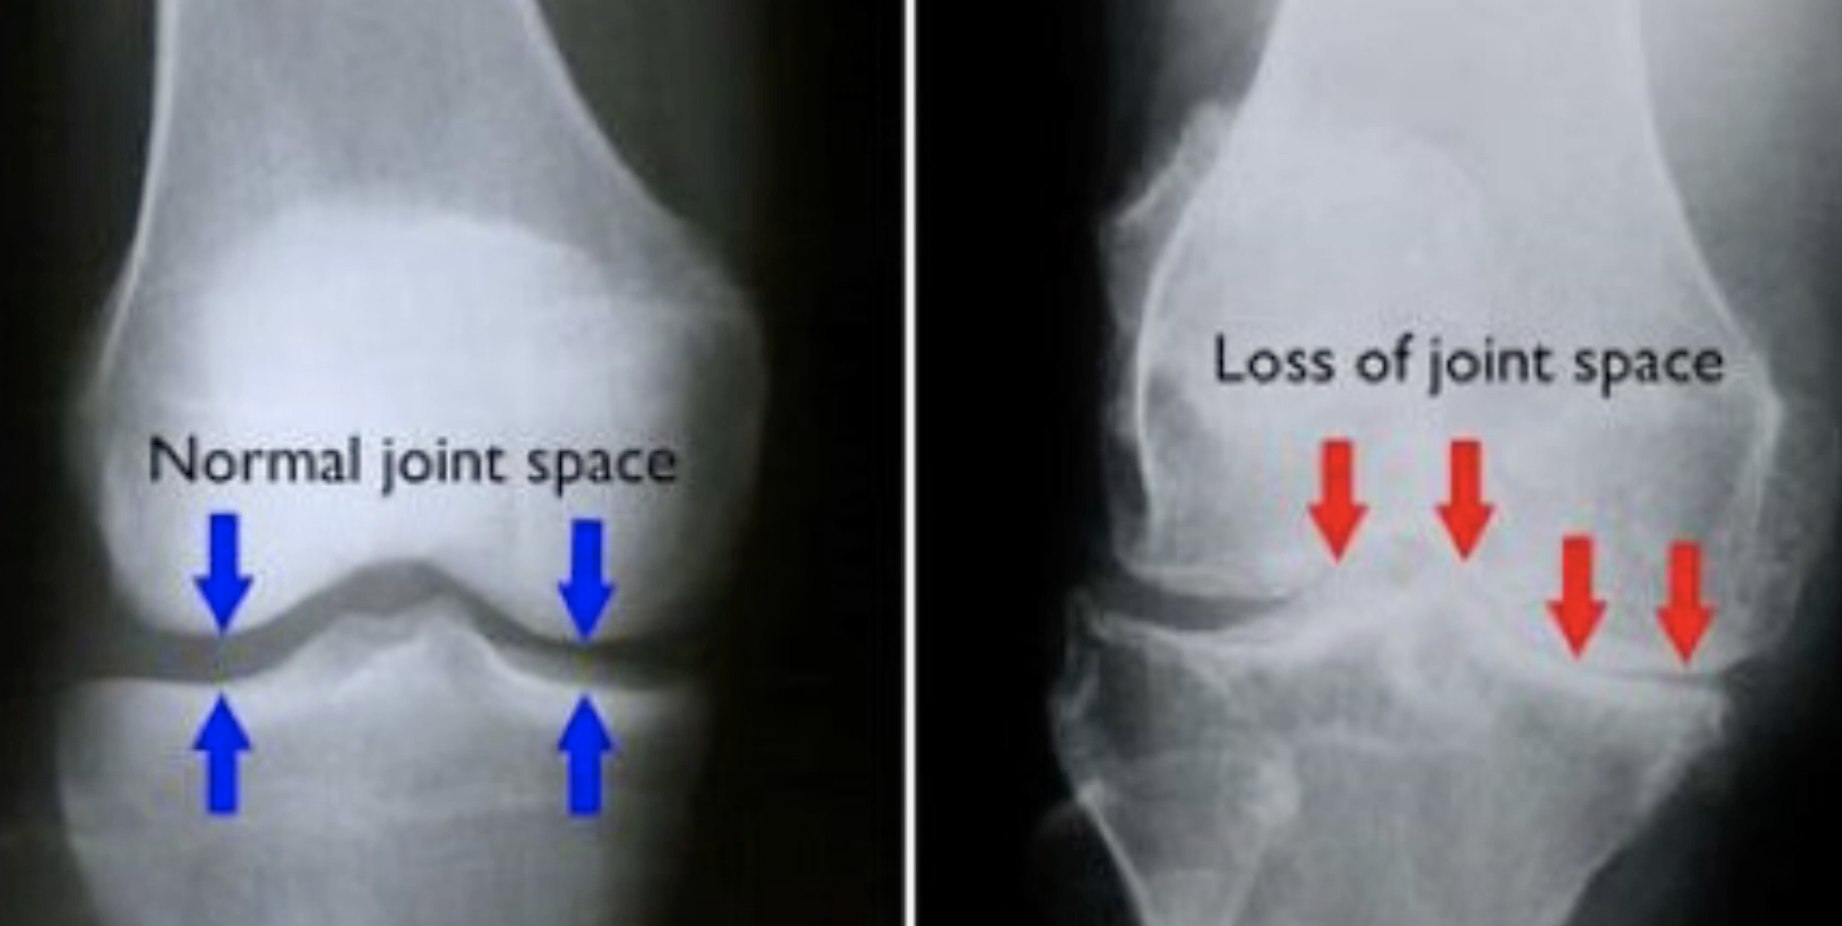

下圖是兩張涉及膝關節的X光片,左邊有藍色箭嘴的X光片,是健康的膝關節,右邊有紅色箭嘴的,是出現了退化性關節炎的膝關節。

在左邊X光片中,4個藍色箭嘴指著的地方,能清楚見到一條「通道」,其實在「通道」中,存在著軟組織,它們能在骨與骨之間,發揮緩衝減震作用。

在右邊X光片中,因為膝蓋已退化,所以見不到那條「通道」,減震能力亦削弱,亦即是人們經常提到的「半月板水分流失」。最終,因為軟組織沒有了,令骨與骨產生摩擦,骨刺便出現。